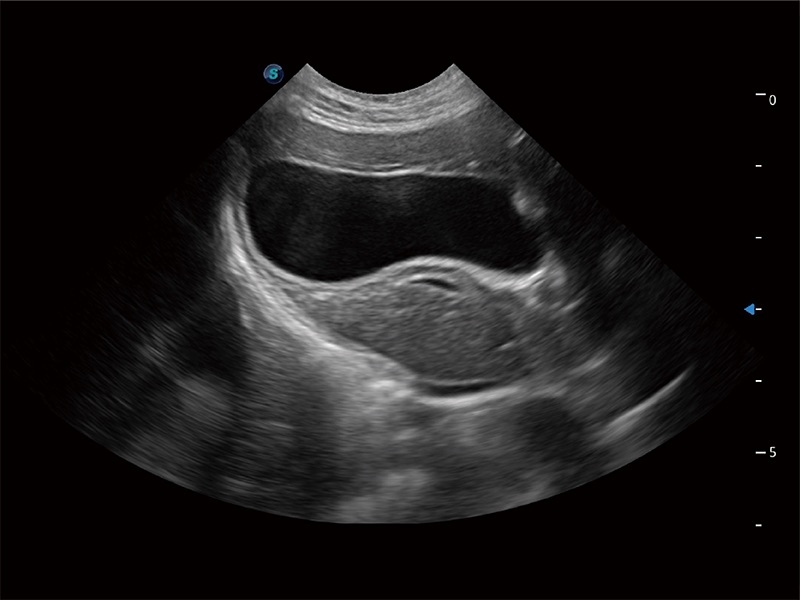

一键自动识别膀胱壁及自动测量膀胱容积,不受膀胱形状和大小的限制,帮助医生快速精准获得测量的数据。

随着取样门位置改变,频谱多普勒包络可进行自动眼踪测量,且可自由配置测量的参数。